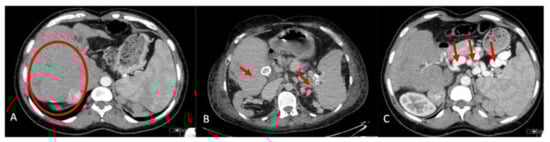

Imaging prior to transplant was available in all but the first six patients in our series. The liver morphology on CT and/or magnetic resonance imaging were characterized by significant central hypertrophy (segment 4 and 1) with atrophy of the right lobe and the left lateral segment (Figure 1A). Nineteen patients (57.6%) were found to have significant SA enlargement (Table 3). Of these, seven (21.2%) had multiple splenic artery aneurysm (SAA) measuring up to 53 mm. In two patients (6%), there were aneurysms in the common and right HA, respectively (Figure 1B,C).

Figure 1.

CT imaging pretransplant. (A) Central hypertrophy of the liver with atrophy of the left lateral segment and right lobe. (B) Calcified hepatic artery and splenic artery aneurysms. (C) Significant enlargement of the splenic artery and multiple aneurysms.